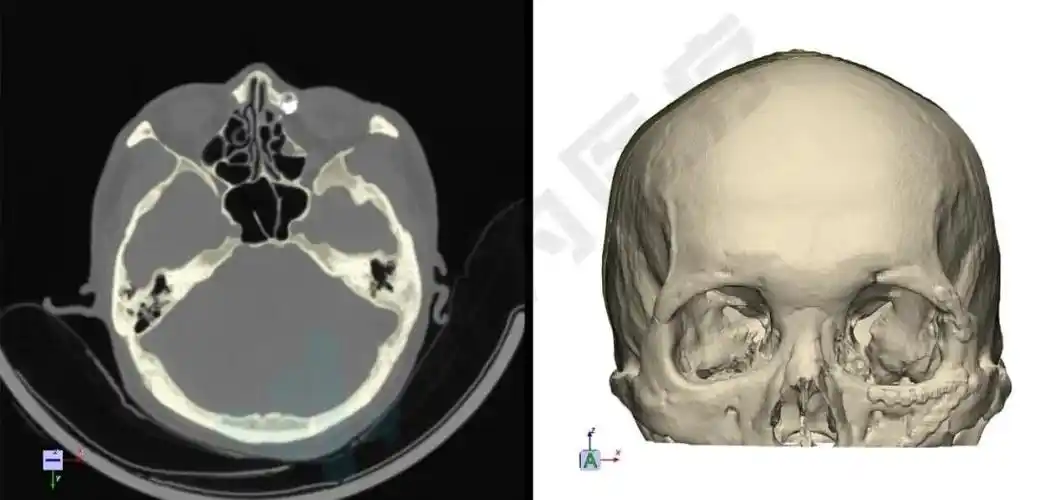

利用3d slicer导入头颅ct,vr重建头颅模型可见头发下隆起的头皮肿物

正文9,头颅ct和三维重建头颅ct扫描通常适用于既往有颅脑损伤病史

先做头部ct三维重建.

检查图像:检查项目:头颅ct平扫,颅骨三维重建.

随后行患儿头颅三维重建检查(图2),并制定相应手术方案.